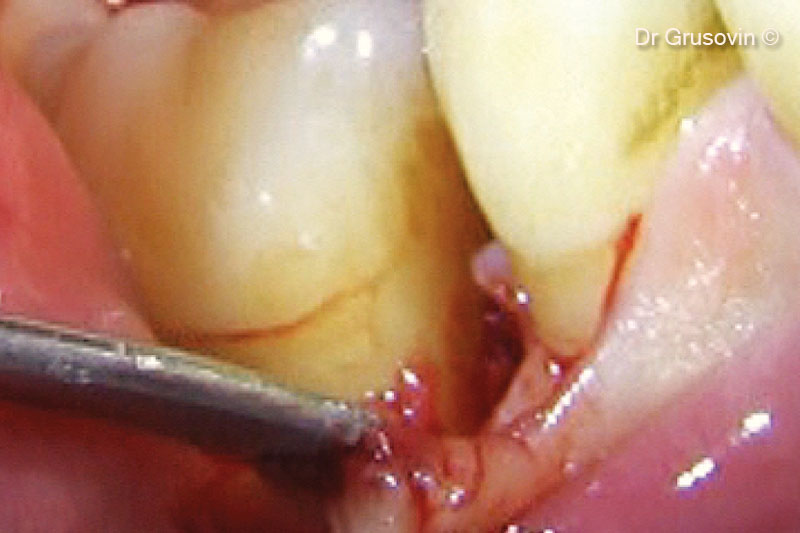

4. Clinical view during surgery: vestibular and distal furcation III involvement